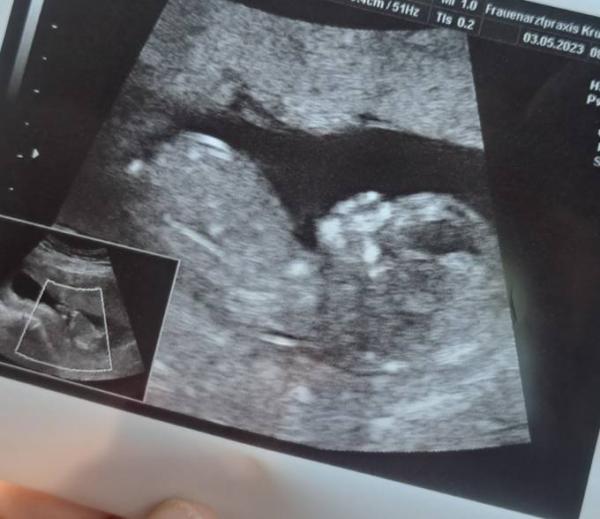

Hello Mädels :) Geht's euch gut? Ich war letzte Woche zur NFT Messung, war schön das kleine Wusel wiederzusehen Im US war alles gut. Die Untersuchung wurde ergänzend zum Harmony Test gemacht. Ist noch jemand unter euch, der ihn auch macht oder machen lassen möchte? Geschlecht lassen wir auch mitbestimmen. Ich muss gestehen ich bin wirklich fasziniert von der "Technik". Bei meiner Tochter gab's das damals noch nicht. (Vor fast 16 Jahren ). Viele scheinen ja auch damit zu hadern. Ich sehe das alles entspannt und rational. Bin halt schon 35 und im Zweifel ist Wissen Macht ;) Da ich übrigens selber immer gerne US Bilder gucke, packe ich euch meins von 12+4 mal rein. Laut Nub (sieht man nicht auf dem Bild) eventuell ein Mädchen Lieben Gruss!